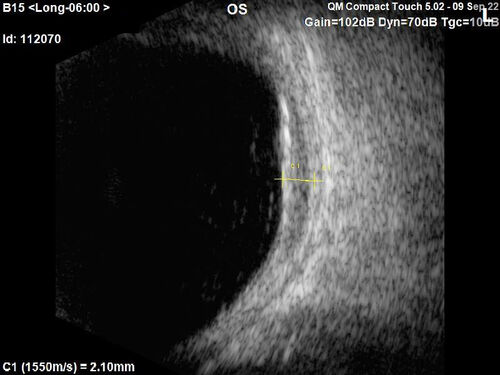

Large chronic choroidal nevus

Autofluorescence image shows guttering at the bottom of the lesion suggesting chronicity. This was documented 23 years prior to these photos